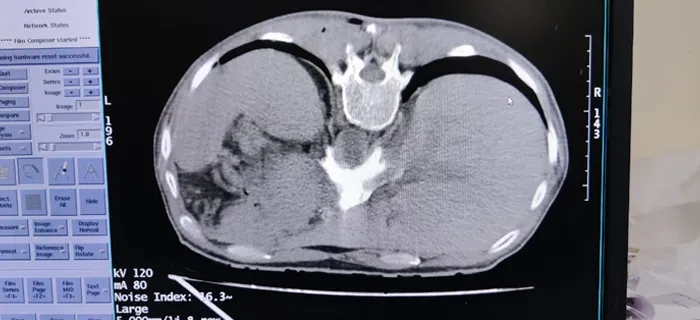

CT Scan Services for Advanced Diagnostic Imaging

CT scans provide detailed cross-sectional images of the body, helping doctors diagnose various complex conditions with greater accuracy.

Our CT imaging services support evaluation of:

- Brain disorders

- Stroke-related conditions

- Trauma and injuries

- Lung diseases

- Internal bleeding

- Abdominal conditions

- Spine-related problems

At Swagat Hospital, we focus on accurate imaging and timely reporting to support faster medical decisions.